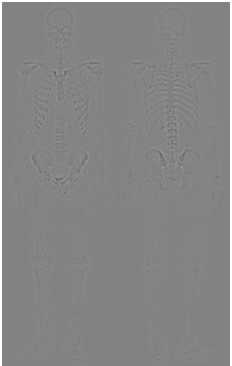

다른 방법은 어떤 방법이 있을 까요? 그 방법은 영상 그래디언트의 스무딩된 버전의 마스크를 사용하는 것입니다. 이러한 과정을 가능한 이유는 미분의 특성에 기인합니다. 라플라시안 필터는 애초에 2차 미분 연산입니다. 따라서 세세한 디테일 개선에는 좋은 결과를 얻을 수 있습니다. 하지만 노이즈가 많은 입력 영상을 받으면 출력 영상 역시 노이즈가 많게 됩니다. 하지만 로버츠나 소벨 연산과 같은 1차 미분 연산자는 라플라시안 필터에 비해서 노이즈나 미세한 디테일에 적은 반응을 보이고, 노이즈나 미세한 디테일을 얻는다고 해도 스무딩을 통해 제거 가능합니다. 따라서, 그래디언트 기반의 필터링을 통해서 엣지를 추출한 뒤 혹시나 남아있는 노이즈를 제거하기 위해 스무딩을 적용하는 것을 샤프닝된 영상의 입장에서는 골격의 마스크로 볼 수 있기 때문에 두 영상을 곱한 결과를 사용하는 것이 합리적입니다. 이를 위해서 위의 사진과 같이 입력 영상에 소벨 연산을 적용하게 됩니다.

다음으로 기울기 영상에 스무딩을 적용하여 약간의 노이즈를 제거해줍니다. 그러면 이를 마스크로 취급하고 샤프닝된 영상과 곱을 취해줍니다.

그 결과 영상 내의 강한 엣지들이 더 많이 남아있으며 노이즈는 라플라시안만 활용한 것에 비해서 더 줄어든것을 관찰할 수 있습니다. 이제 강한 엣지 영상을 샤프닝하는 데 사용해주면 됩니다.